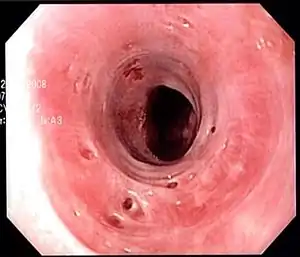

| Endoscopic image of esophageal intramural pseudodiverticulosis demonstrating the flask-like outpouchings of the esophageal wall. | |

Esophageal intramucosal pseudodiverticulosis is typically diagnosed at the time of endoscopy of the esophagus. Endoscopy shows evidence of the pseudodiverticulae, which are typically numerous, appear like pits in the wall, and may be preferentially located in the upper esophagus.[2][4] The mucosal lining of the esophagus may be inflamed, and this can be seen on endoscopy or on biopsy; the mucosa, however, may also be normal if esophagitis is not the cause of the pseudodiverticulosis. The condition must also be excluded from esophageal cancer, which may be done at the time of endoscopy, or which may require esophageal biopsy.[2]